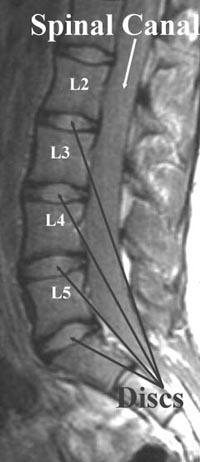

This shows what normal discs look like in the lower back. The central part has a significant amount of water within it and behaves something like jello or like an expensive gel-filled seat cushion.

This inner part of the disc, the nucleus, is a bright gray on these pictures. The outer part of the disc, the annulus, is a tough, fibrous layer that is strong.

It keeps the softer nucleus in place. It is dark on these pictures and looks the same as the edges of the bone. The inner part of the bone, the bone marrow, contains cells that produce red and white blood cells